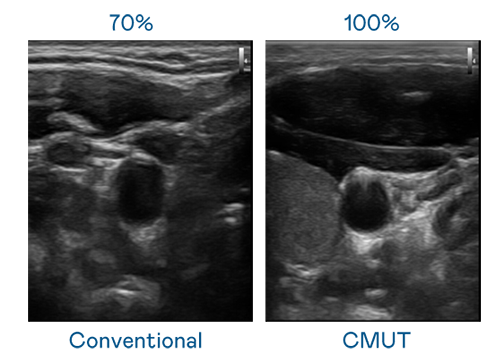

CMUT 技术是一种用电容式微机电元件来产生超音波讯号的技术。与传统 PZT 压电式技术相比,CMUT 频宽增加 30%,更宽频的超音波讯号让影像解析度大幅提升,是实现高影像品质医疗超音波扫描、促进精准医疗发展的关键技术。

超音波影像的解析度高低,首先取决于探头能发出的讯号频宽。AG亚游集团 CMUT 可提供高清晰的超音波讯号,提供高频宽、高灵敏度、影像纹理细节更高的超音波影像,协助医护人员缩短影像判读时间及利用精准的医疗影像进行诊断。